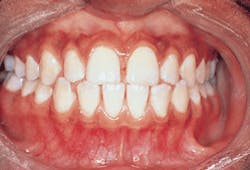

A 14-year-old African-American female who was diagnosed with localized juvenile periodontitis can be seen in figure 1. Observe that there is no apparent gingival inflammation. The supragingival plaque score for this patient was low. Supragingival and subgingival calculus accretions were not detected. Minimal or no inflammation (as well as little or no calculus) is a clinical finding that is very common for patients who are in the early stages of localized juvenile periodontitis.

Figure 1: A 14-year-old African-American female diagnosed with localized juvenile periodontitis.